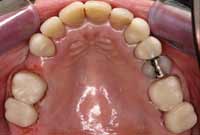

Figure 1

The patient was unhappy with the esthetics of her smile. Note the uphill cant to the left.

Figure 2

Several occlusal flags included crowded anteriors and abfractions.